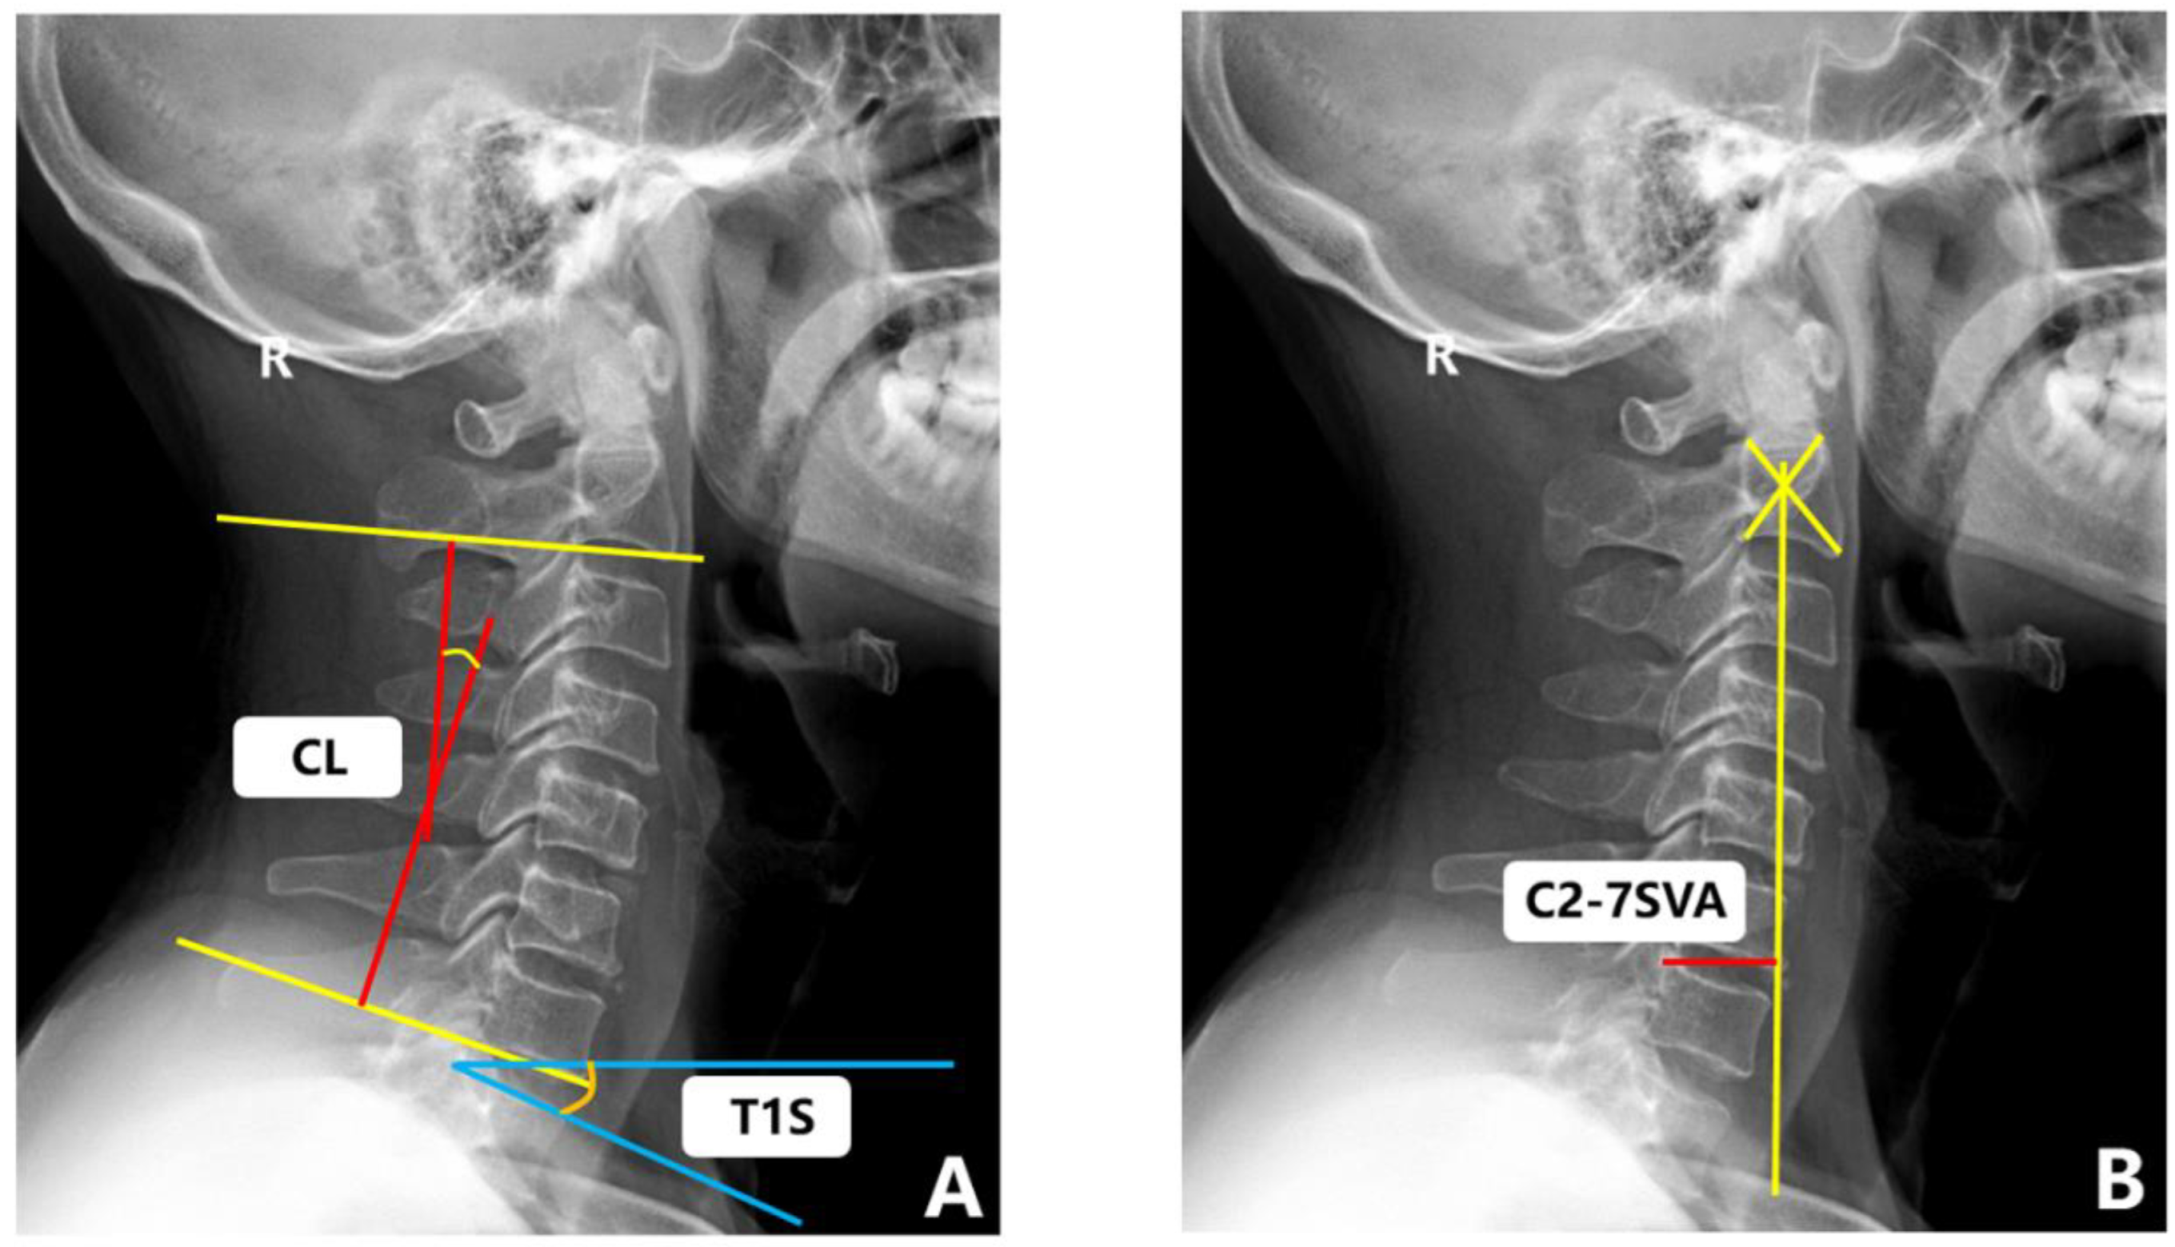

There was no significant difference between Group A and Group B regarding gender, BMI, smoking history, drinking history, number of lesion segments, surgical methods, surgical time, blood loss, the CCI, CCI classification, T1S, C2–7SVA, CL (F), T1S (F), C2–7SVA (F), CL (E), T1S (E), C2–7SVA (E), CL (ROM), T1S (ROM), C2–7SVA (ROM), MSCC, MCC, TA, TAR, CR, CCR, pre-VAS and pre-NDI (p > 0.05). There were significant differences in age, duration of symptoms, the CL and the pre-mJOA (p < 0.05) (Table 3 and Figure 6).

Figure 6.

(A) Age difference between the two groups (independent-sample t-test). (B) CL difference between the two groups (independent-sample t-test). (C) Pre-mJOA difference between the two groups (independent-sample t-test). (D) Duration of symptoms (months) difference between the two groups (Mann–Whitney U test). Asterisks represent data with large bias.